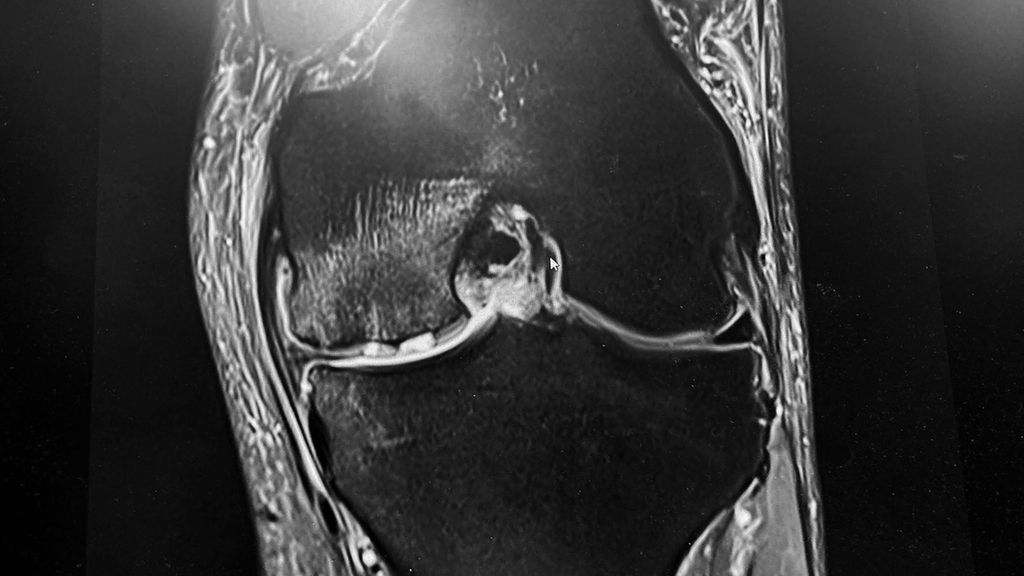

Abb. 2: Knochenmarködem mit subchondraler Insuffizienzinfrakturierung (SCIF) bei Knorpelschaden und Meniskusverlust bei einer 60-jährigen Patientin mit plötzlicher Zunahme der Belastungsschmerzen. Therapie ist hier mit Entlastung und Bisphosponaten iv angezeigt.

Eine der am häufigsten beobachteten Veränderungen des subchondralen Knochens sind die subchondralen Knochenmarksläsionen (BML), auch bekannt als subchondrales Knochenödem, definiert als eine Veränderung der MRT-Signalintensität des Knochenmarks, die auf T1- und T2-gewichteten Bildern zu sehen ist und am besten mit Fettsuppressions-STIR-Sequenzen dargestellt wird. Das Vorhandensein von subchondralem BML weist im Allgemeinen auf eine Form der Verletzung hin, die das Ergebnis eines akuten Traumas, von Stoffwechselanomalien, einer vorübergehenden Überbelastung infolge einer Gelenkknorpelverletzung oder einer chronischen Überbelastung wie bei OA sein kann. Diese Verletzungen führen zu einem Ungleichgewicht zwischen den Reizen und der Fähigkeit des Knochens, sich zu remodellieren und den physiologischen und funktionellen Zustand wiederherzustellen. In der MRT wird dies durch Veränderungen der Knochensignalintensität dargestellt. Das Muster dieser Veränderungen kann je nach Ätiologie der subchondralen BML unterschiedlich sein, was sich auch auf die Prognose und die mögliche Behandlung auswirkt. Die subchondrale BML, die sekundär zu Gelenkknorpeldefekten auftritt, weist im Allgemeinen auf eine Beeinträchtigung der Gesundheit des subchondralen Knochens hin und kann entweder einen reversiblen oder einen irreversiblen Prozess darstellen. Ein Beispiel für einen reversiblen Zustand ist der typische „bone bruise“, der nach einer ACL-Ruptur festgestellt wird, während die BML, die bei OA-Knien auftritt, zu einer Insuffizienzfraktur oder sogar zu einer Osteonekrose führen kann, was einen irreversiblen Prozess darstellt. Diese Osteonekrose kann dann im Kollaps des subchondralen Knochens enden, was im Verlauf des Morbus Ahlbäck das Endstadium darstellt.